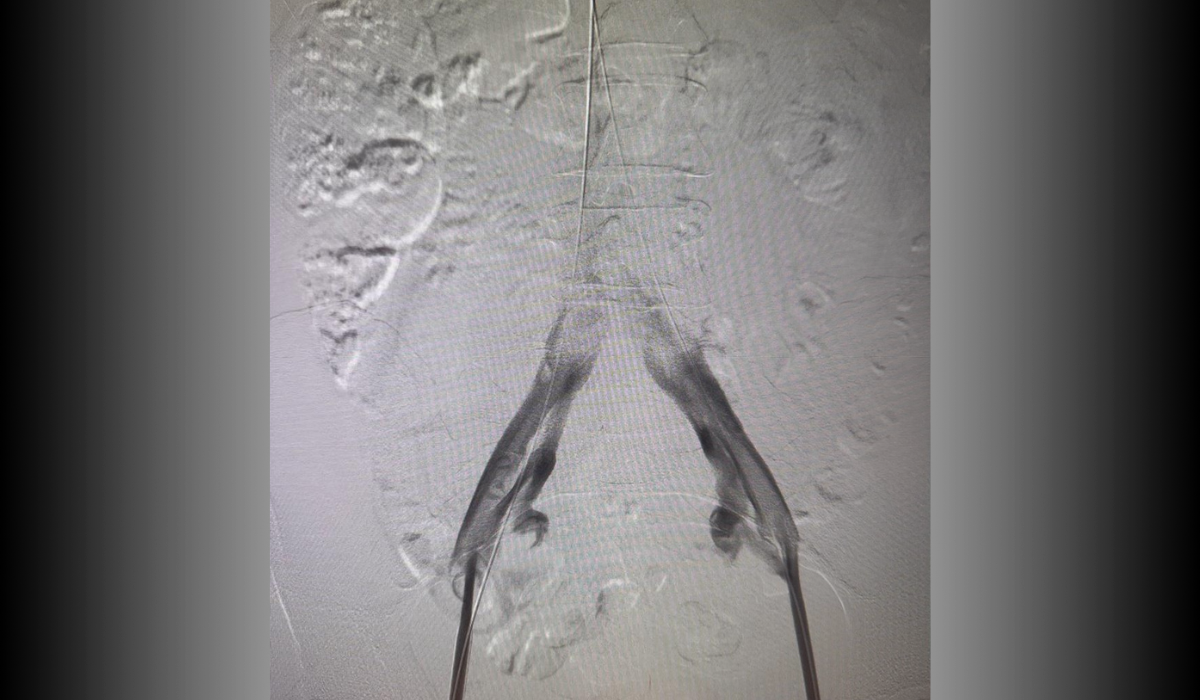

Antes: Oclusión bilateral ilíaca

Antes

Oclusión de ambas venas ilíacas/Sindrome de congestión pélvica

Después: Reconstrucción con stents

Después

Reconstrucción con stents. Flujo normalizado y resolución clínica.